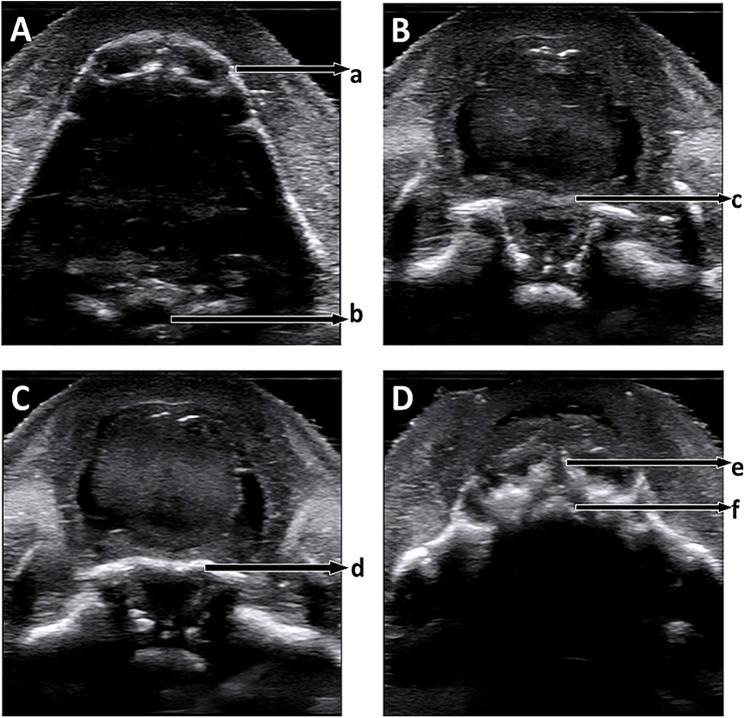

A software was designed and programmed based on "sequential sector scan through the oral fissure" and three-dimensional ultrasound. The three-dimensional ultrasound volume data of the fetal face were imported into the software. Then, the median sagittal plane was taken as the reference interface, the anterior upper margin of the mandibular alveolar bone was selected as the fulcrum, the interval angles, and the number of layers of the sector scan were set, after which the automatic scan was performed. Thus, the sector scan sequential planes of the mandibular alveolar bone, pharynx, soft palate, hard palate, and maxillary alveolar bone were obtained in sequence to display and evaluate the palate. In addition, the feasibility and accuracy of the software in fetal palate displaying and screening was evaluated by actual clinical cases.

Full views of the normal fetal palates and the defective parts of the cleft palates were displayed, and relatively clear sequential tomographic images and continuous dynamic videos were formed after the three-dimensional volume data of 10 normal fetal palates and 10 cleft palates were imported into the software.

基于“经口裂顺序扇形扫描”和三维超声设计并编写了一个软件。将胎儿面部的三维超声容积数据导入软件中。然后,以正中矢状面作为参考界面,以下颌牙槽骨的前上缘作为支点,设置扇形扫描的间隔角和层数,自动进行扫描。从而依次获得下颌牙槽骨、咽部、软腭、硬腭和上颌牙槽骨的扇形扫描序列平面,以显示和评估腭部。此外,通过实际临床病例评估软件在胎儿腭部显示和筛查中的可行性和准确性。

正常胎儿腭部和腭裂缺陷部分的全貌得以显示,将 10 例正常胎儿和 10 例腭裂胎儿的三维容积数据导入软件后,形成了相对清晰的连续断层图像和动态视频。